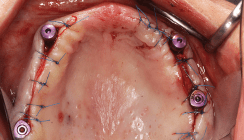

Als vorbereitende Maßnahme wurden die insuffizienten Implantate 13 und 43 in Lokalanästhesie entfernt. Anschließend erfolgte in ITN unter perioperativer antibiotischer One-shot-Prophylaxe (1,5 g Spizef i.v.) zunächst die Entnahme von Corticalis-Spongiosa-(CS-) Spänen und ausreichend Spongiosa vom rechten anterioren Beckenkamm. Durch ein zweites OP-Team wurde währenddessen das Transplantatlager im Oberkiefer vorbereitet. Es folgte eine Sinusbodenelevation beidseits mit der zwischenzeitlich homogenisierten und in Eigenblut zwischengelagerten Spongiosa. Zusätzlich wurde eine Onlay-Osteoplastik im Oberkiefer beidseits Regio 14–24 mit zwei CS-Knochenblöcken und Spongiosa vorgenommen. Die Fixierung der Knochenblöcke erfolgte mit Osteosyntheseschrauben in Zugschraubentechnik (Abb. 4). Schließlich wurden die mit der homogenisierten Spongiosa ausmodellierten Blocktransplantate mit einer Kollagenmembran (PARASORB RESODONT) abgedeckt. Es folgte anschließend eine Onlay-Osteoplastik im Unterkiefer Regio 35–45 mit zwei CS-Blocktransplantaten und homogenisierter Spongiosa. Dabei wurden auch die schüsselförmigen Knochendefekte im Bereich der ehemaligen Implantate 33 und 43 mit Spongiosa aufgefüllt (Abb. 5a und b). Die Fixierung der transplantierten Knochenspäne erfolgte mittels Osteosyntheseschrauben in Zugschraubentechnik mit konsekutiver Membranabdeckung (Abb. 5c). Nach knöcherner Einheilung der Transplantate wurden die Osteosyntheseschrauben entfernt und simultan Titanschraubenimplantate (Element RC Inicell) Regio 13, 16, 23, 26 bzw. 32, 34, 42, 45 inseriert. Einen Monat nach Insertion der Implantate erfolgte zur Korrektur der Weichgewebeverhältnisse eine Vestibulumplastik Regio 32–34 und 42–45.

Prothetische Phase

Nach stabiler knöcherner Einheilung der Implantate und Konsolidierung der Weichteilverhältnisse konnte die prothetische Versorgung mit präzisionsgefrästen NEM-Stegen im Ober- und Unterkiefer auf den Implantaten 13, 16, 23, 26, 32, 34, 42 und 45 vorgenommen werden (Abb. 6a–c). Der steggelagerte Überwurf wurde als abnehmbare Brückenkonstruktion in Galvanotechnik gestaltet (Abb. 6d).